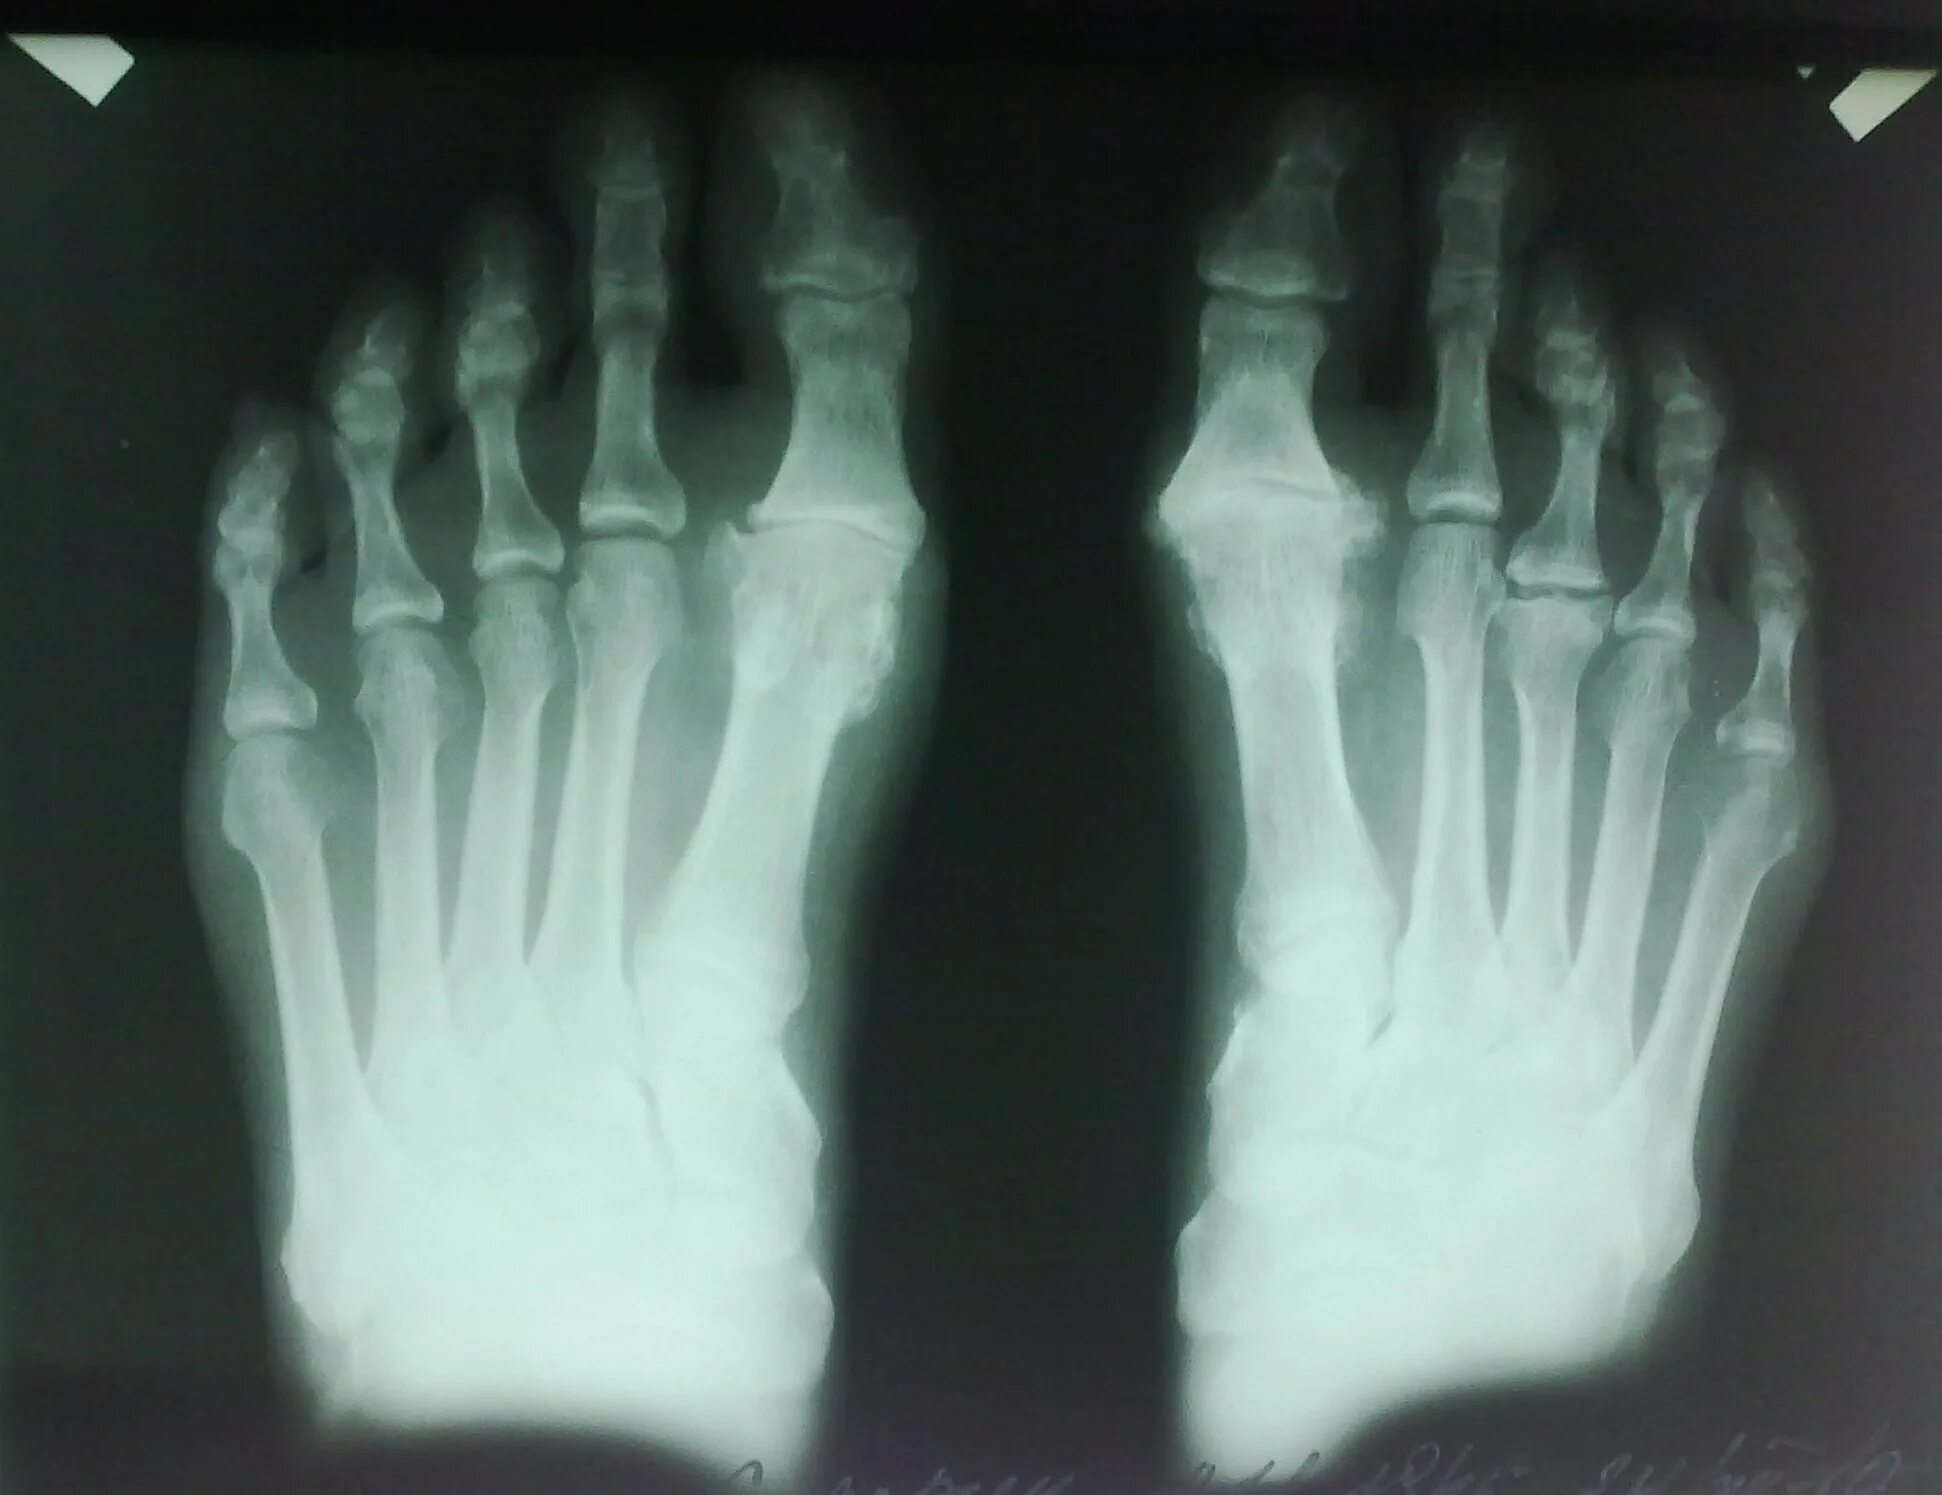

Келлера 3